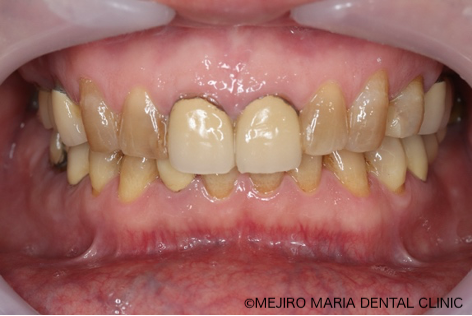

患者様は、長年にわたり臼歯部(奥歯)の噛み合わせの調子が悪いことと、食事の際に痛みを感じることを主訴に来院されました。前歯部から口腔内を確認すると大きなトラブルは確認できませんが、レントゲン撮影と口腔内診査を行うと、多数の臼歯部の歯牙(歯)が歯根破折により抜歯を余儀なくされる状況でした。

今回の症例は、臼歯部の崩壊により前歯部に負荷がかかり始め「咬合の崩壊」の手前の状態でした。患者様も、徐々に歯が悪くなっていくことを十数年もの間、恐怖に感じていたものの、歯科医院の受診からは遠ざかっていたようです。初診時に「最近では食事することもつらい」と訴えていたことから、患者様のQOL(生活の質)は著しく低下していたことが予想されました。この状況をできる限り早く、確実に改善することが求められる症例でした。

現在は、食事や会話の際にも口元を気にすることがなくなったことから、日常生活でのストレスは軽減したと考えられます。